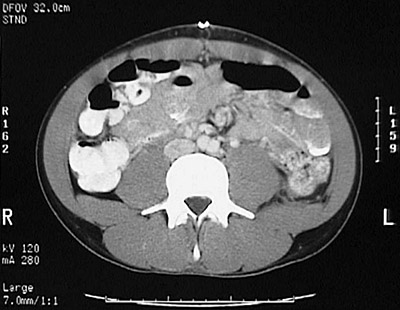

[L4] This is a normal abdominal CT scan with contrast demonstrating the colon and small intestine and aorta at bifurcation and left ureter and inferior vena cava and psoas muscle and in the lower abdomen.